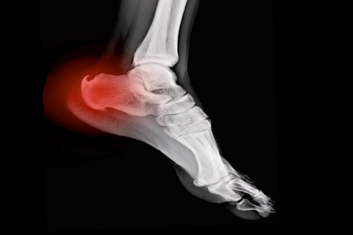

Tym razem szczególnie polecam tekst o też, o fitoterapii, która wzmacnia działanie antybiotyków. Dzięki mocy związków roślinnych możemy ponownie uwrażliwić lekooporne bakterie na antybiotyki! Ponadto w tym numerze Stary Doktor podaje zalecenia dotyczące przeciwdziałania ostrodze piętowej oraz suchości pochwy. Detektyw Medyczny radzi, jakie zioła pomogą na świąteczne przejedzenie i związane z nim dolegliwości, a nasza Naturopatka podpowiada, jak zadbać o zdrowy pęcherz.

Porady z notatnika Starego Doktora - Ostroga piętowa

Omawiamy najbardziej naglące potrzeby, podając obiecujące alternatywne sposoby leczenia. Takie, które – jak udowodniono(!) – działają. Nasz Stary...